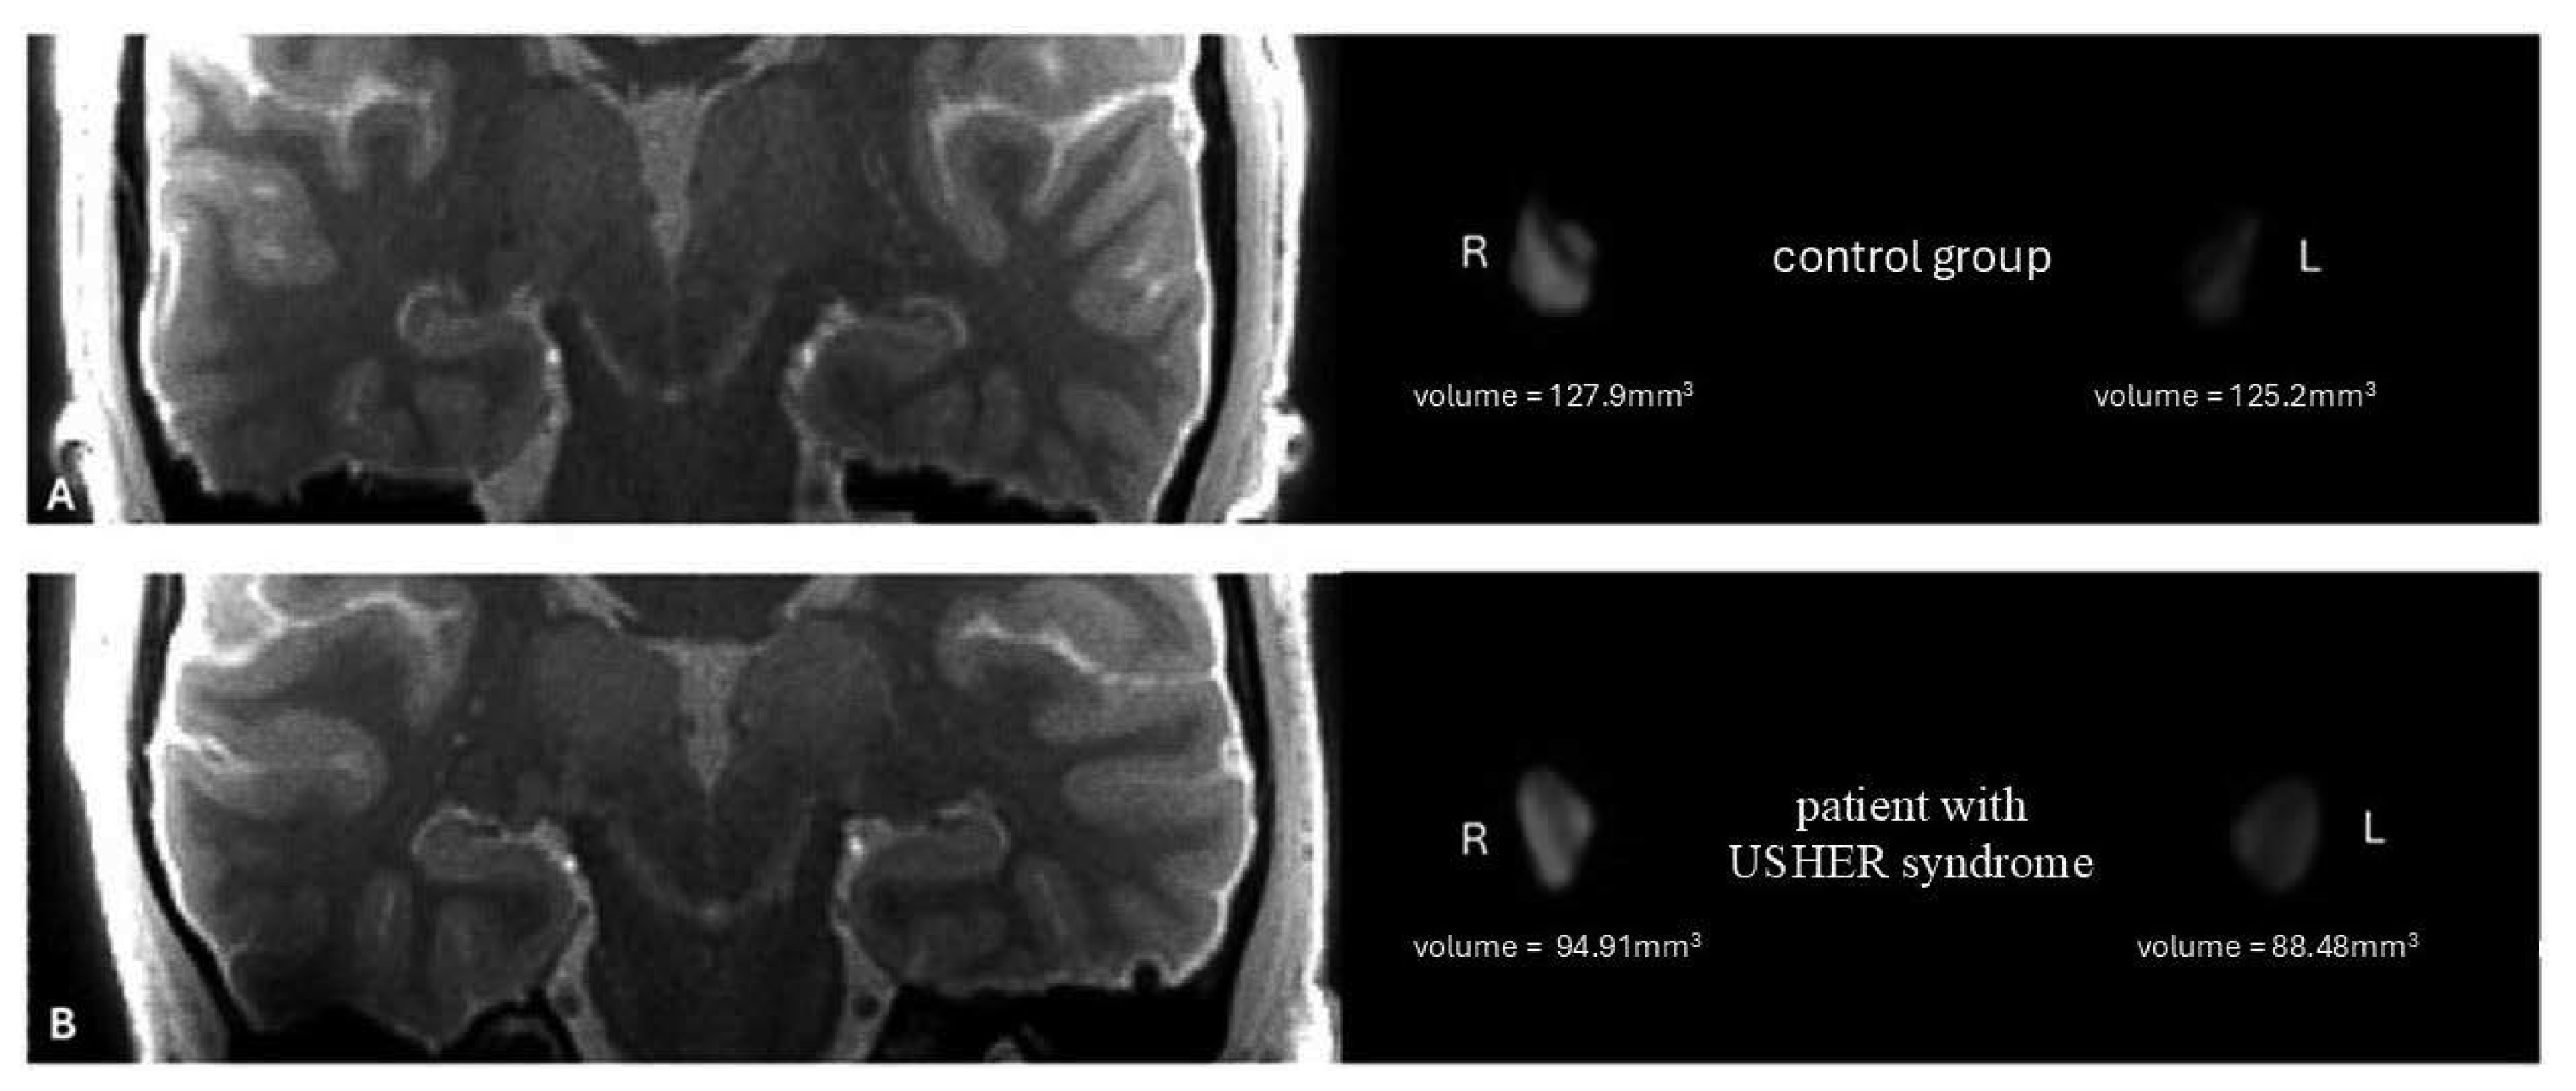

- Kosior-Jarecka, E.; Pankowska, A.; Polit, P.; Stępniewski, A.; Symms, M.R.; Kozioł, P.; Żarnowski, T.; Pietura, R. Volume of Lateral Geniculate Nucleus in Patients with Glaucoma in 7Tesla MRI. J. Clin. Med. 2020, 9, 2382. [Google Scholar] [CrossRef] [PubMed]

- Schmidt, M.A.; Knott, M.; Heidemann, R.; Michelson, G.; Kober, T.; Dörfler, A.; Engelhorn, T. Investigation of lateral geniculate nucleus volume and diffusion tensor imaging in patients with normal tension glaucoma using 7 tesla magnetic resonance imaging. PLoS ONE 2018, 13, e0198830. [Google Scholar] [CrossRef]

- Jonak, K.; Krukow, P.; Jonak, K.E.; Radzikowska, E.; Baj, J.; Niedziałek, A.; Symms, M.; Stępniewski, A.; Podkowiński, A.; Osuchowska, I.; et al. Decreased Volume of Lateral and Medial Geniculate Nuclei in Patients with LHON Disease-7 Tesla MRI Study. J. Clin. Med. 2020, 9, 2914. [Google Scholar] [CrossRef]